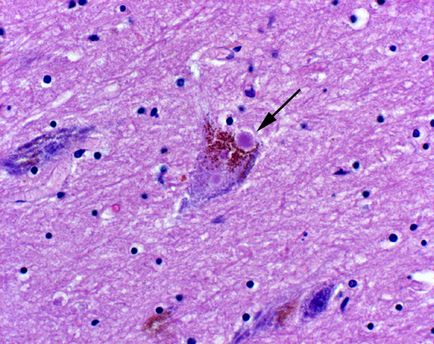

Az egyre világosabb, hogy az idegrendszer a bél felelős nemcsak az emésztést, részben a fejlődés tanulmányok, amelyek megerősítik, hogy a második agy is lényeges, hogy széles körű agyi betegségek. A Parkinson-kór, például motor merevsége, gipomimiya, károsodott szabályozása motoros funkciók által okozott tömegveszteség a dopamin-termelő agysejtek. Heiko Braak (University of Frankfurt, Németország) felfedezett egy fehérjét felhalmozódást (Lewy-testes) a dopamin-termelő idegsejtek a bél plexus.

Lewy testek a neuron. (A fényképek kölcsönzött innen)

Lewy testek - találhatók az idegsejtekben az agy a Parkinson-kór, úgy véljük, hogy ez a patológiás felhalmozódása a fehérjék és más vegyületek az oka morfológiai jellemzője és idegsejt-károsodás .. Demencia is ismert, Lewy-testes - mintegy harmada minden esetben a kognitív torzítások, hogy a tünetek a Parkinson-kór anélkül, hogy jelentős memóriazavar. Kb. per.

Felmérése szerepét és Lewy-testes a betegség, akik meghaltak, a Parkinson-kór, H. Braak úgy véli, hogy a kialakulását kóros sejtek kezdődik a bél neuronok. Az okok, hisz, kizárólag külső, olyan vírusok, amelyek terjedt felfelé a vagus ideg.

Sőt, a jellegzetes jelei kár az idegsejtekben az agy talált emberek Alzheimer-kór is jelen vannak az idegsejtek az agyban második. Autista emberek hajlamosak emésztési problémák, amelyek ugyanazt a genetikai markerek mutációk károsítja az idegsejtek az agyban. Bár még csak a legelején a megértés közötti kölcsönhatás az agy és a gyomor-agy, az agy egy második ablak a fő patológiai az agy azt mondja, P. Pasriksha (Johns Hopkins University, Baltimore-ban, Maryland). „Elméletileg tudjuk használni a biopszia az idegszövet a bél a korai diagnózis és értékelje a hatékonyságát kezelés.”